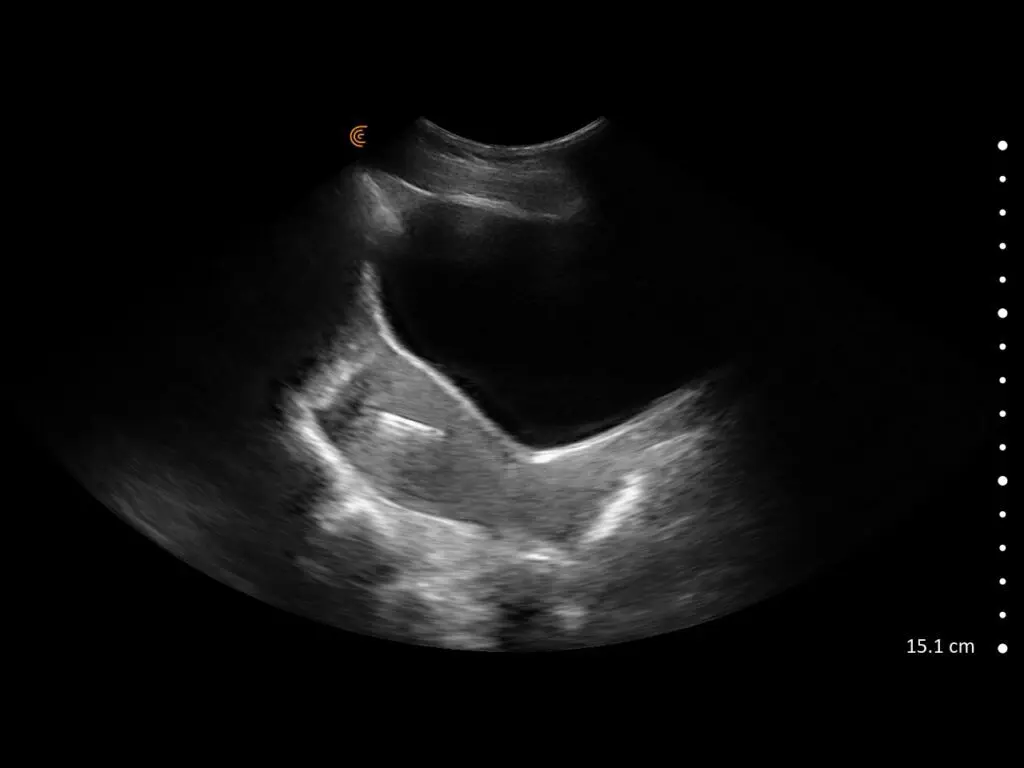

ProbeFix Dynamic is a new device that enables high-quality ultrasound measurements during dynamic exercise by keeping an ultrasound probe in place, allowing for muscle monitoring during intense movement and creating new research possibilities in muscle imaging.